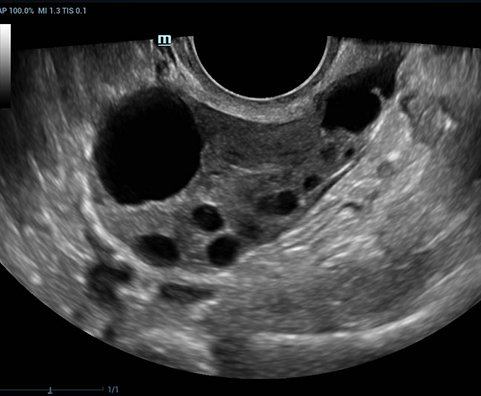

Smart FLC

Smart FLC автоматически определяет количество фолликулов и рассчитывает объем каждого из них используя 3D-данные яичника. Всё это обеспечивает точную оценку размера фолликулов, что особенно важно при ЭКО.

DE11-3U – датчик для внутриполостных исследований и плода. Поддерживает THI, 4D, iScape, биопсию, Color M и работает на всех режимах кроме CWD

DE10-3U – датчик для внутриполостных исследований и плода. Поддерживает THI, 4D, iScape, биопсию, Color M и работает на всех режимах кроме CWD